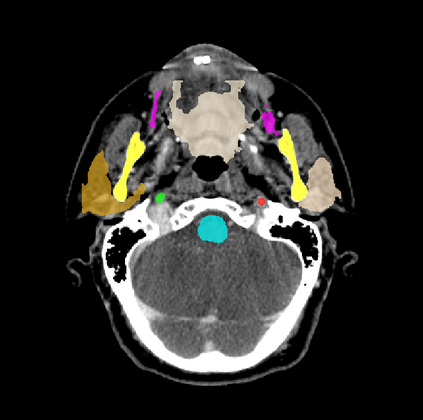

Organ at risk (OAR) segmentation is a critical process in radiotherapy treatment planning such as head and neck tumors. Nevertheless, in clinical practice, radiation oncologists predominantly perform OAR segmentations manually on CT scans. This manual process is highly time-consuming and expensive, limiting the number of patients who can receive timely radiotherapy. Additionally, CT scans offer lower soft-tissue contrast compared to MRI. Despite MRI providing superior soft-tissue visualization, its time-consuming nature makes it infeasible for real-time treatment planning. To address these challenges, we propose a method called SegReg, which utilizes Elastic Symmetric Normalization for registering MRI to perform OAR segmentation. SegReg outperforms the CT-only baseline by 16.78% in mDSC and 18.77% in mIoU, showing that it effectively combines the geometric accuracy of CT with the superior soft-tissue contrast of MRI, making accurate automated OAR segmentation for clinical practice become possible. See project website https://steve-zeyu-zhang.github.io/SegReg